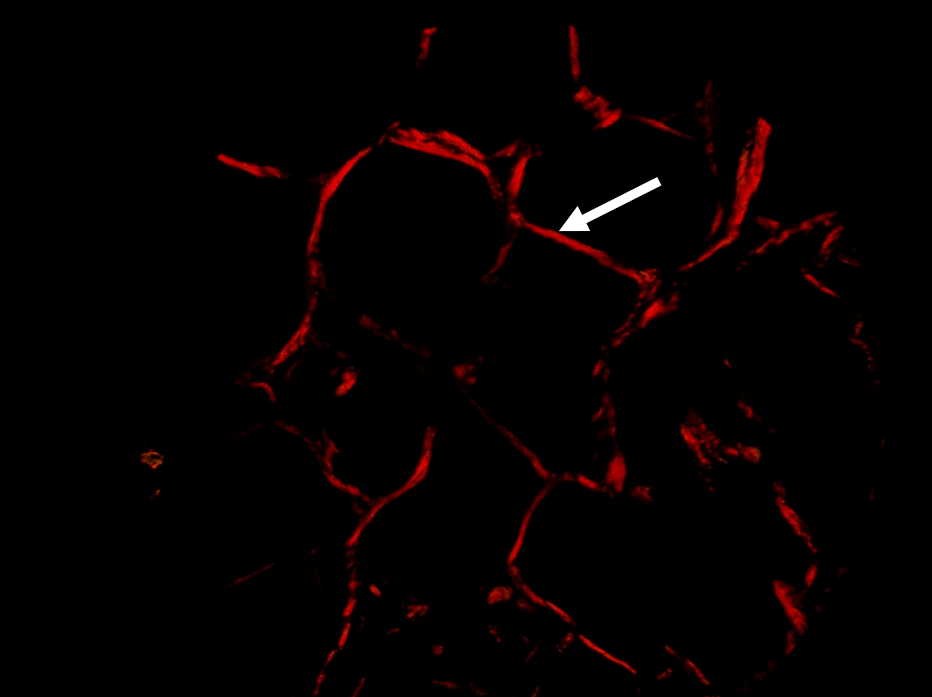

Adenoma pleomórfico. Colágeno Tipo III (flechas). Picrosirius red. Microscopía de polarización.

El estroma juega un rol importante en los procesos tumorales de invasión y metástasis. Las fibras de colágeno tipo I son el principal componente estructural del estroma en distintos tumores. Sin embargo, hay muy pocos estudios en los tumores de glándulas salivales. Basándonos en estos antecedentes el objetivo de la presente comunicación fue estudiar las características del colágeno con Picrosirius red/polarización en tumores benignos y malignos de glándulas salivales para evaluar su posible rol en los mecanismos de progresión tumoral. Cortes histológicos de adenoma pleomórfico, carcinoma adenoide quístico y carcinoma epitelial mioepitelial se colorearon con H/E y Picrosirius red y se examinaron con microscopio de polarización. La birrefringencia del colágeno con Picrosirius/polarización resultó diferente en el estroma de los tumores malignos (carcinoma adenoide quístico y carcinoma epitelial mioepitelial), con predominio de colágeno I, en comparación con el tumor benigno (adenoma pleomórfico), con predominio de colágeno III. El diferente perfil de coloración en las fibras colágenas producidas en el estroma de los tumores analizados podría relacionarse con diferentes mecanismos de expansión tumoral, los que fueron poco estudiados en los tumores de glándulas salivales. Más estudios son necesarios para obtener resultados más concluyentes que contribuyan al diagnóstico, pronóstico y tratamiento.